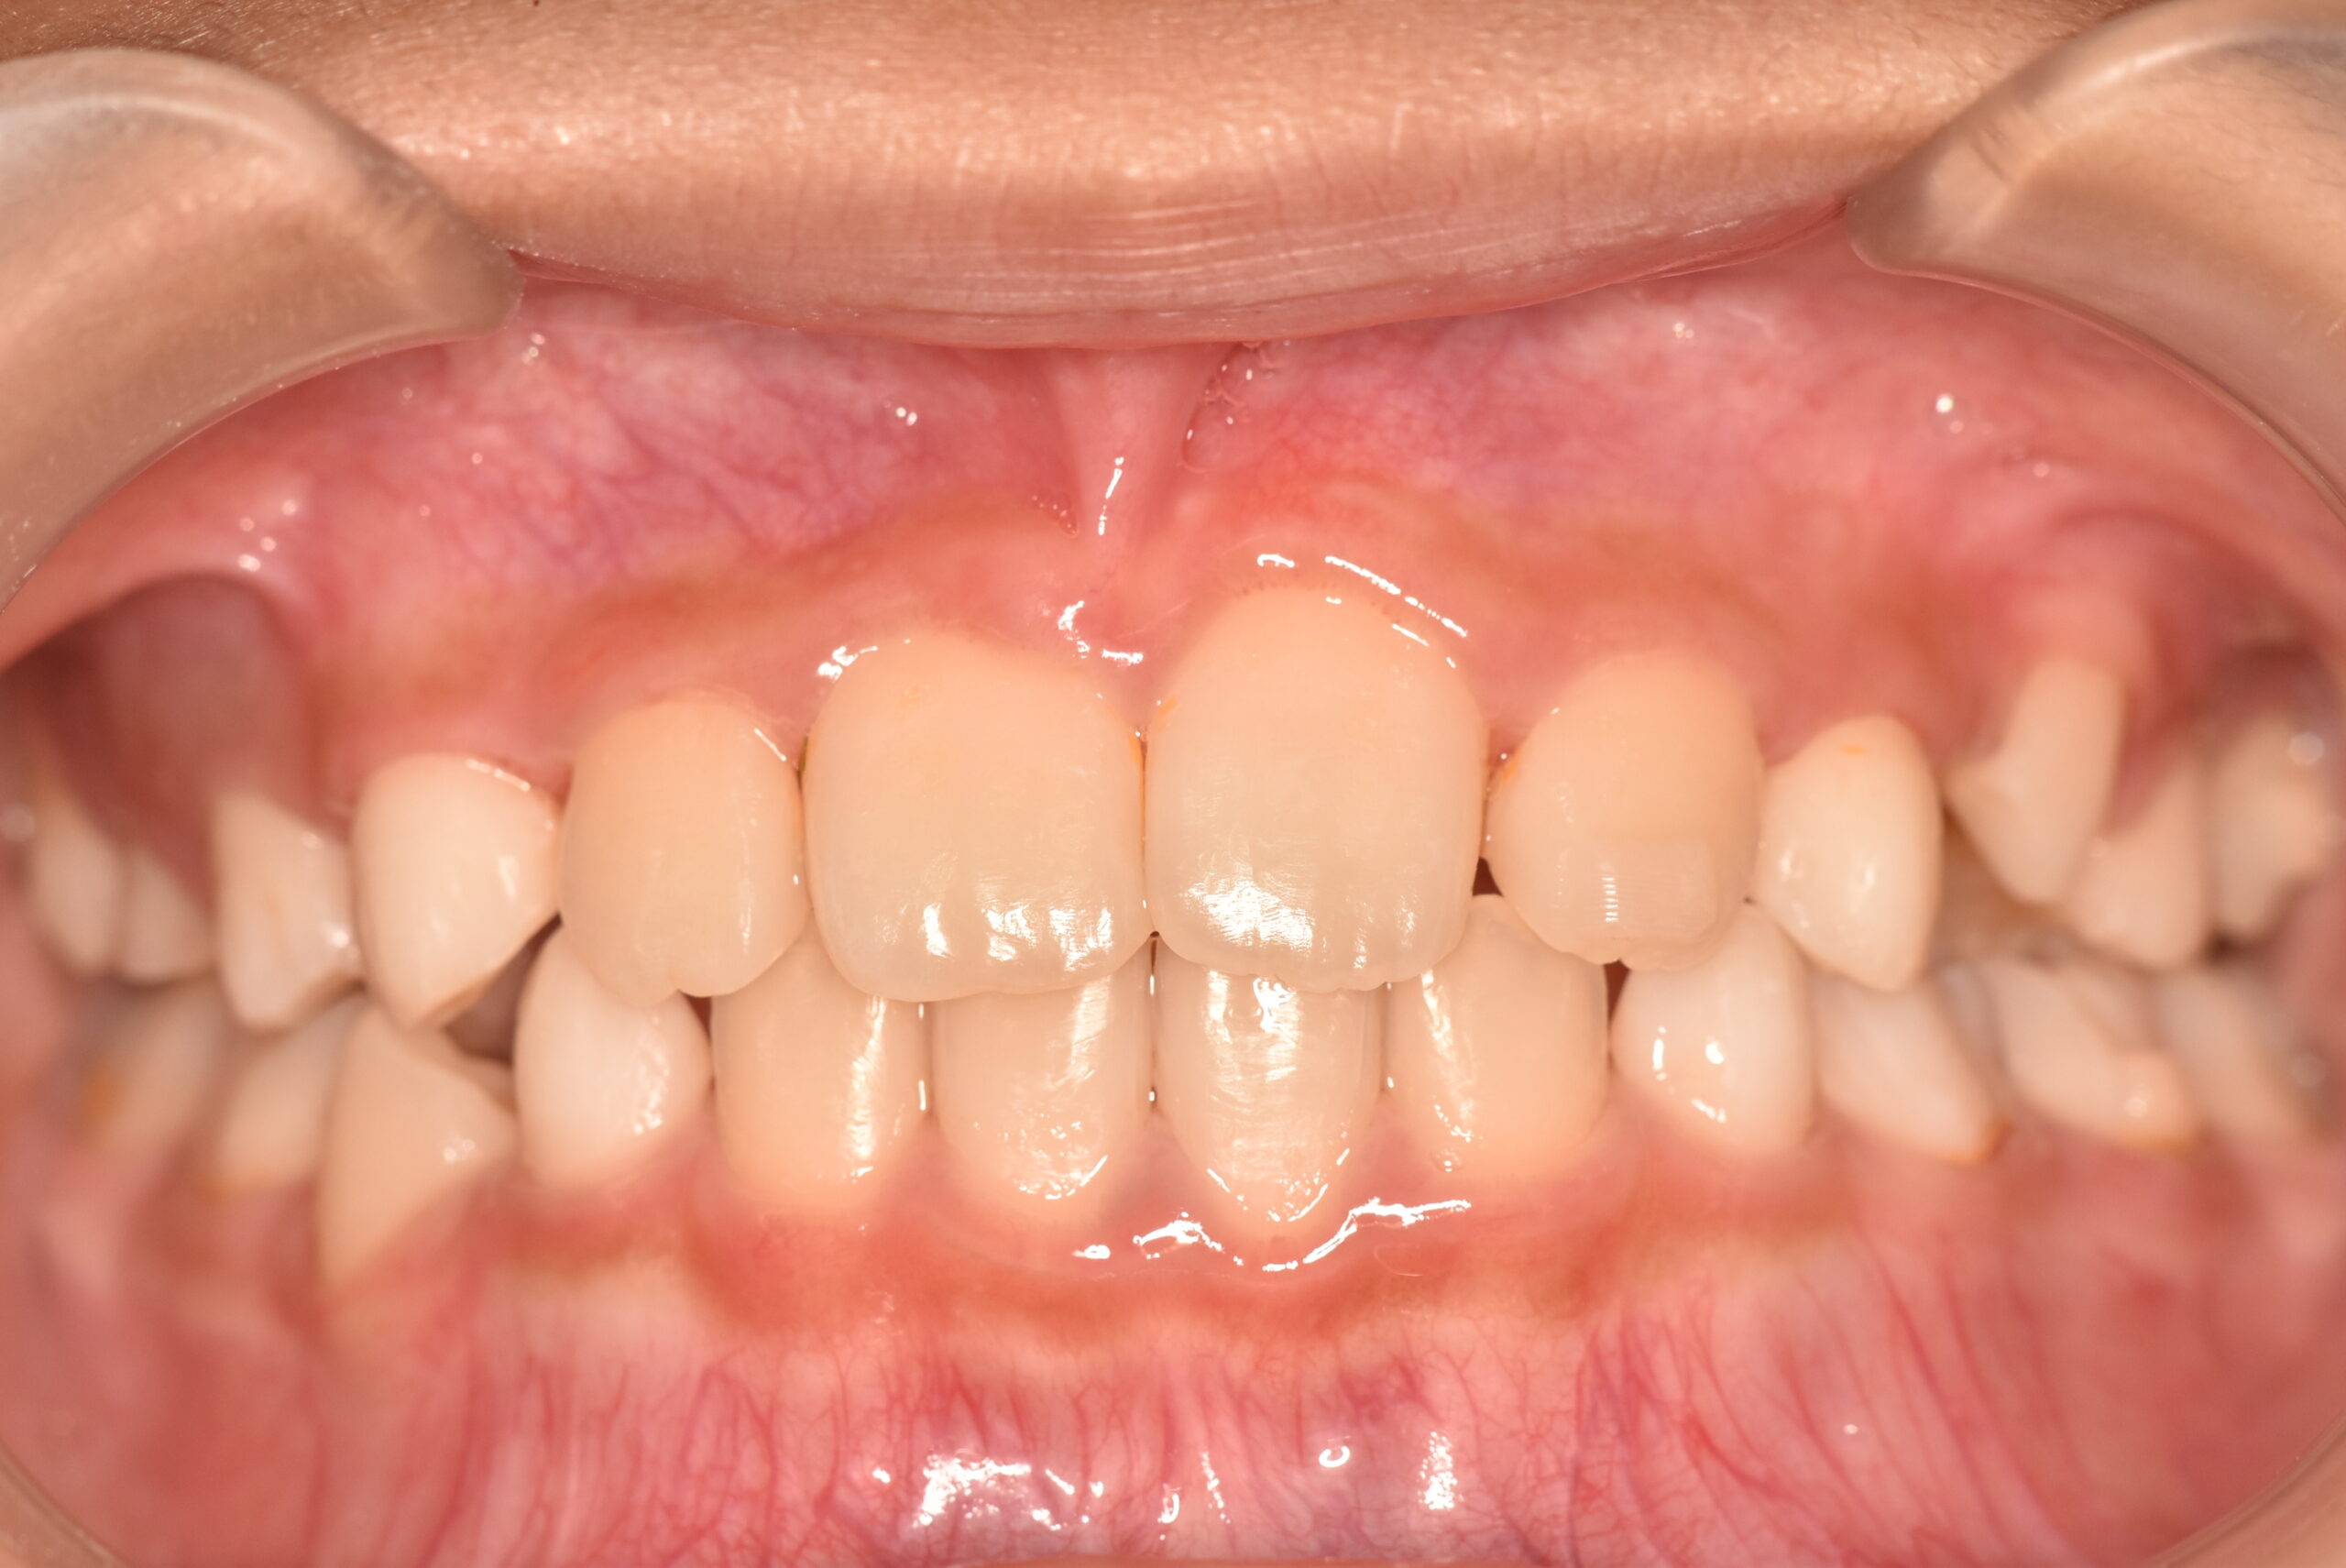

| 治療内容の詳細 | 初診時9歳3ヶ月の男児で、前歯が磨きにくく虫歯になりやすいことを気にされ来院されました。 検査の結果、前歯部叢生を伴うアングルⅠ級不正咬合と診断しました。 治療としてはマウスピース矯正(インビザラインファースト)で配列を行い、上下顎の側方拡大により永久歯の萌出スペースを確保しました。 治療期間は、1年6ヶ月でした。 今後、永久歯(側方歯)の生え変わりまで経過観察を行います。 |